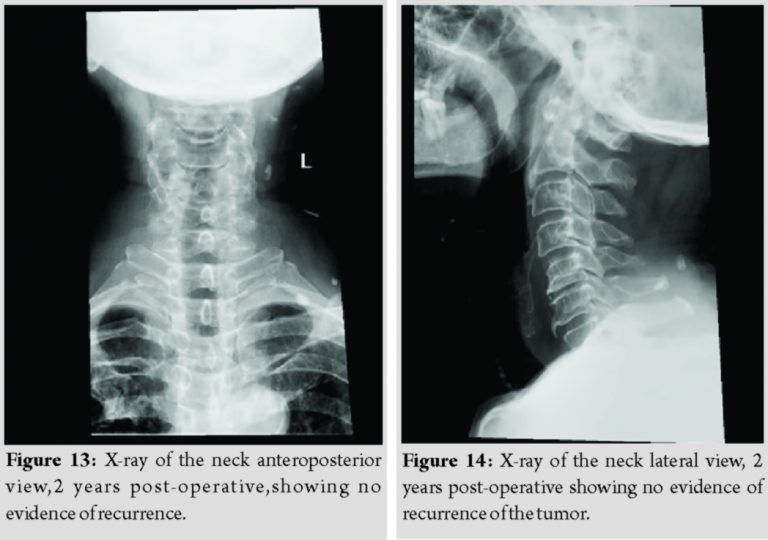

The post-operative period was uneventful and recovered completely. Power of the right upper limb and, movements of the shoulder are unaffected. The patient was started postoperatively on nonsteroidal anti-inflammatory drugs (NSAIDs) for a period of 1 month. The patient was not willing for radiotherapy and hence was deferred. He has been on regular follow-up for the past 2 years. There is no evidence of residual disease or recurrence of the tumor (Fig. 13 and 14).